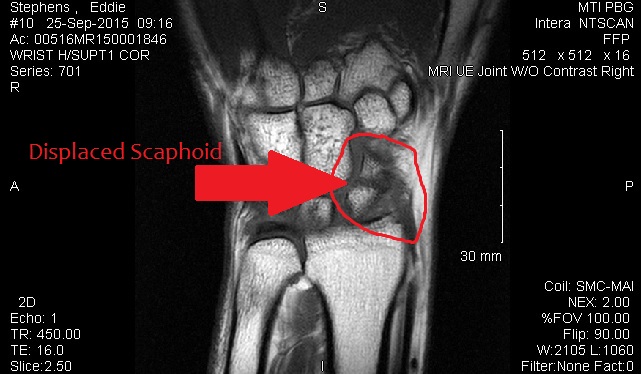

Per orthopedic surgeon. Elbow fracture healing nicely. Wrist a little more concerning. MRI scheduled for 9/25/2015 to determine if surgery/pins needed to repair wrist.

UPDATED SEPTEMBER 25, 2015

MRI of displaced bones in wrist. Also have significant ligament damage.